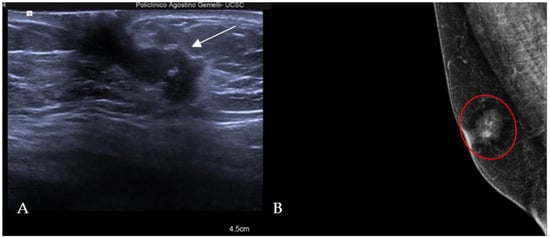

The most common histological subtype of primary malignant breast lesions in men is invasive ductal carcinoma (IDC) [27,28], shown in Figure 7.

Figure 7.

A 60-year-old man with gynecomastia presenting a retroareolar lump on the right breast with nipple retraction and without nipple discharge. Histological examination revealed an invasive ductal carcinoma (ER + 90%, PR + 60%, HER2 score 1+). Ultrasound examination (A) shows a hypoechoic irregular mass (white arrow) in the retroareolar region, with lobulated margins. A mammography (B) shows an irregular hyperdense retroareolar mass with lobulated margins (red circle).

IDC typically originates from the terminal duct–lobular unit [28,29]. Clinical features include a palpable unilateral retroareolar mass with nipple retraction and skin thickening [28,29]. Around 25% of cases may present with bloody nipple discharge [28]. IDC can be associated with ductal in situ components in up to 50% of cases [30]. Mammographically, IDC appears as a retroareolar irregular high-density mass with spiculated or micro-lobulated margins [30,31]. Unlike in women, IDC in men is rarely associated with microcalcifications due to the involution of the ductal system caused by the absence of estrogen and progesterone stimulation [28,29]. Ultrasonography reveals solid, hypoechoic, and irregular masses with margins ranging from microlobulated to spiculated [32]. Papillary carcinoma (PC) is the second most common invasive subtype of MBC and has a higher incidence in men compared to women [33]. PC is characterized by neoplastic proliferation of cells with fibrovascular stalks lacking an intact myoepithelial cell layer [34]. It typically presents with bloody nipple discharge and occurs in the subareolar region. Mammographically, PC may exhibit well-circumscribed or spiculated margins, while ultrasound imaging may reveal a dilated duct or cyst, often appearing as a complex cyst with solid papillary projections along the cyst wall [35,36] (Figure 8).